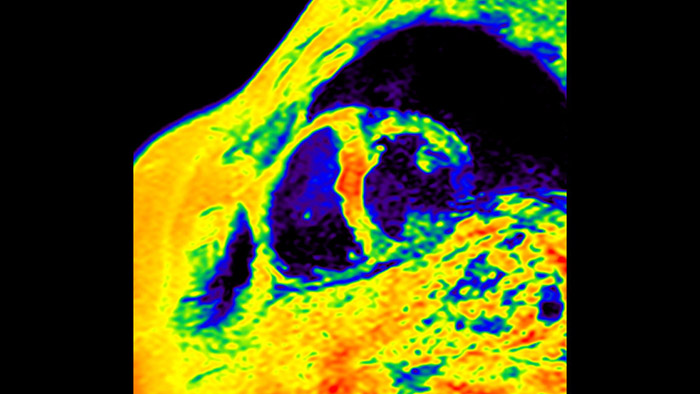

O IntelliSpace Portal MR Caas7,8 Strain9 ajuda no diagnóstico e monitorização do paciente ao proporcionar parâmetros globais de deformação, tais como deformação longitudinal global (GLS), deformação circunferencial global (GCS) e deformação radial global (GRS), utilizando imagens de RM de eixo curto e longo, bem como descrevendo a deformação do miocárdio, como encurtamento, espessamento e alongamento durante o ciclo cardíaco.